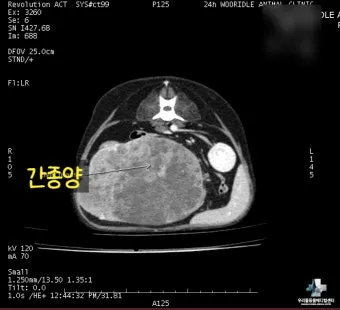

CT와 MRI 검사 - 초음파에서 의심스러운 소견이 발견되면 더 정밀한 검사를 진행해요. 특히 3D 영상으로 종양의 정확한 위치와 크기를 파악할 수 있어서 수술 계획을 세우는 데 필수적이에요.